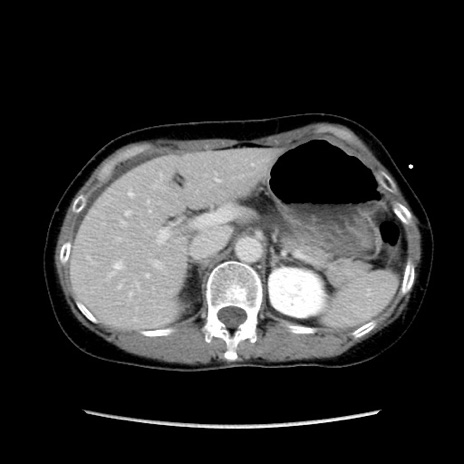

症例32(横断像)

【症例】40歳代 女性

【主訴】上腹部痛、嘔気・嘔吐

【現病歴】約9時間前頃から急に上腹部痛、嘔気、嘔吐が出現。改善しないため救急要請。

【既往歴】子宮頚癌(広汎子宮全摘術、放射線療法)、腸閉塞

【身体所見】腹部:平坦、軟、腸雑音亢進、上腹部を中心に腹部全体に圧痛あり。

【データ】WBC 8400、CRP 0.03